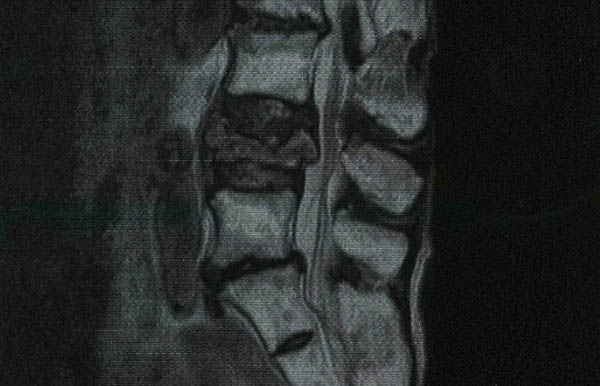

(12)初めての要介護認定調査とMRI…昭和1ケタ女は強かった